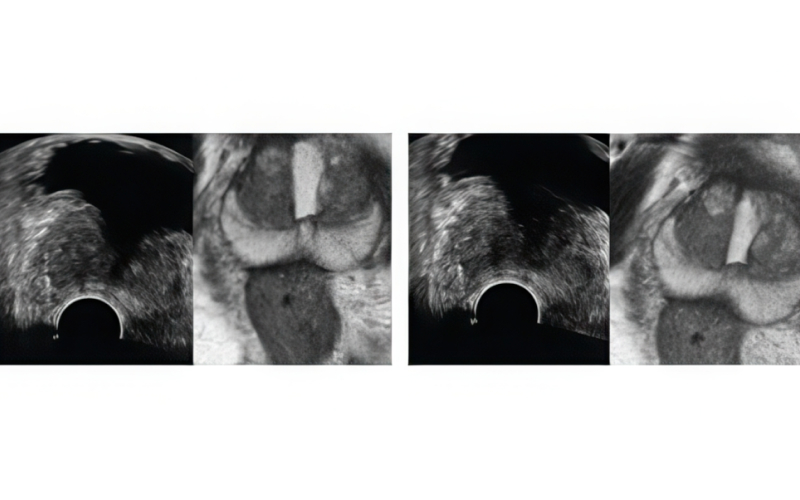

기존 검사는 병변 유무와 관계없이 12군데를 무작위로 채취해 정확도가 낮고 재검 가능성이 높았습니다. 하지만 MR 퓨전 조직검사는 병변을 직접 겨냥해 조직을 채취하므로 진단율이 크게 향상되었습니다.

· 병변을 정확히 채취 · 71.4%의 진단율 · 한 번의 검사로 끝날 확률이 높음 · 통증 ½로 감소 |

· 12군데를 무작위로 채취 · 약 25~35%의 진단율 · 재검 확률이 상대적으로 높음 · 통증 부담이 높음 |